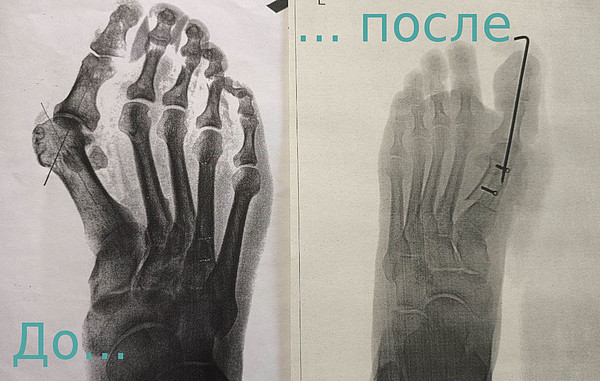

Photo-364стопы

стопы.